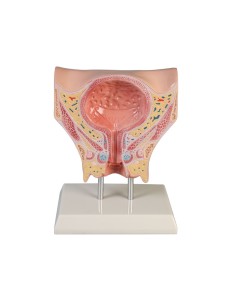

3B Modèle scientifique et gynécologique pour l'entretien avec les patientes P53

Pelvis masculin 3B Scientifique avec ligaments, vaisseaux, nerfs, plancher pelvien et...

Modèle anatomique du squelette du bassin d'un homme 3B Scientific H21/1

3B Bassin scientifique, anatomique Modèle pour illustrer l'accouchement L30